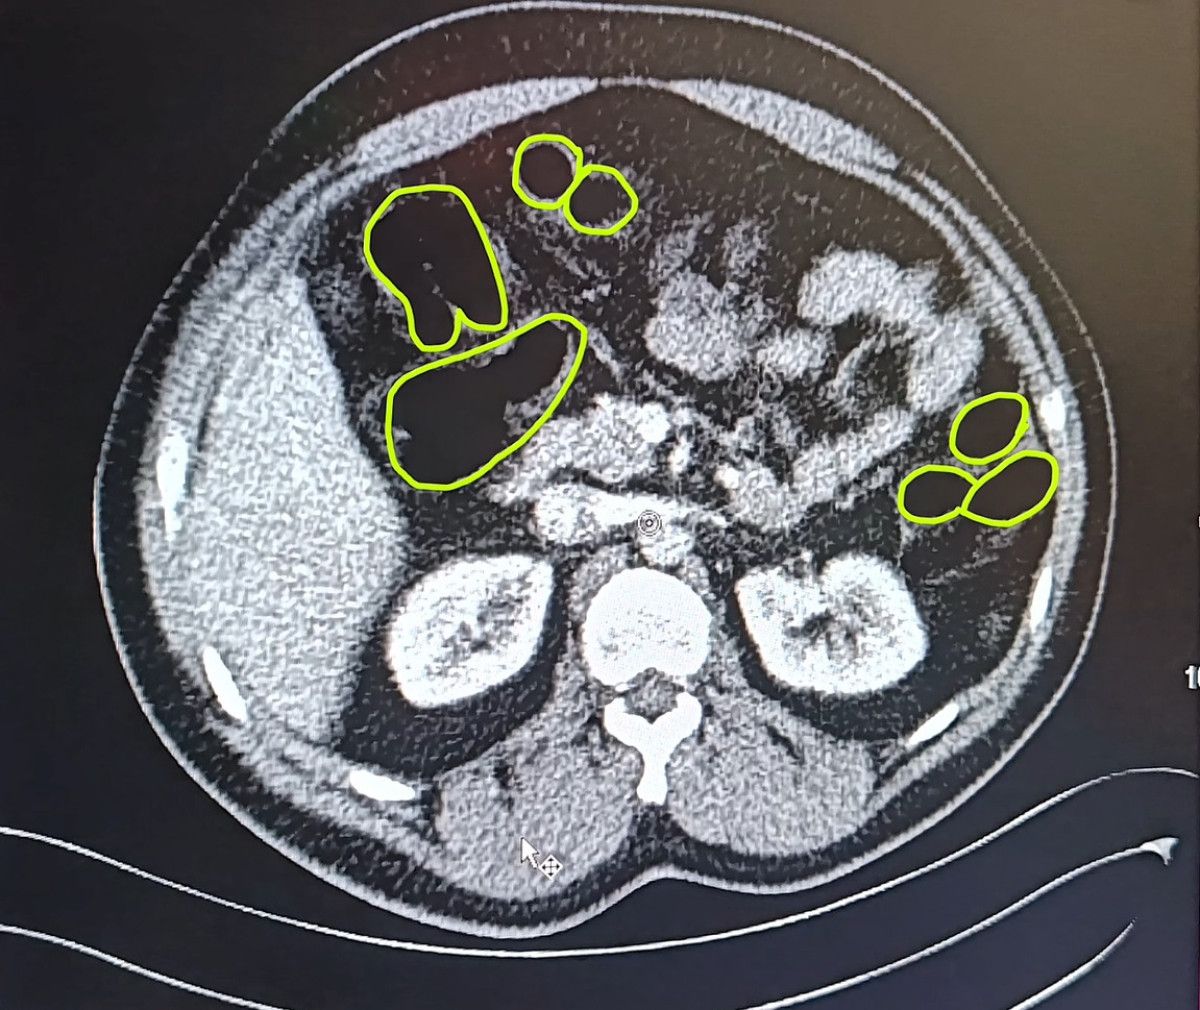

Kayseri Vilayet Jandarma Komutanlığı grupları Kocasinan ilçesi Himmetdede Mahallesi’nde İran asıllı 3 şüphelinin bulunduğu ticari aracı durdurdu.

Araçtaki A.O. (51), M.S. (37) ve P.S.’nin (28) üzerinde yapılan aramada bir ölçü uyuşturucu bulundu.

Zanlıların uyuşturucu unsurları yutmuş olabileceğini kıymetlendiren gruplar bu bireyleri hastaneye götürdü.

MİDELERİNDEN UYUŞTURUCU ÇIKTI

Röntgenlerinde midelerinde uyuşturucu unsur olduğu belirlenen zanlılardan 20 gram çeşitli uyuşturucu unsur ile 117 uyuşturucu hap ele geçirildi.